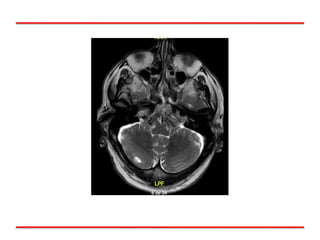

RM Cerebro: 09/16

Lesión Cerebelosa Dª.

RM cerebro Mx Cerebrales (80% a lo largo Enf)

FBC: 09/16 Lesión Endoluminal LSD. Biopsia:09/16 Carcinoma Células Pequeñas RM Cerebro: 09/16 Lesión Cerebelosa Dª. Caso Clínico